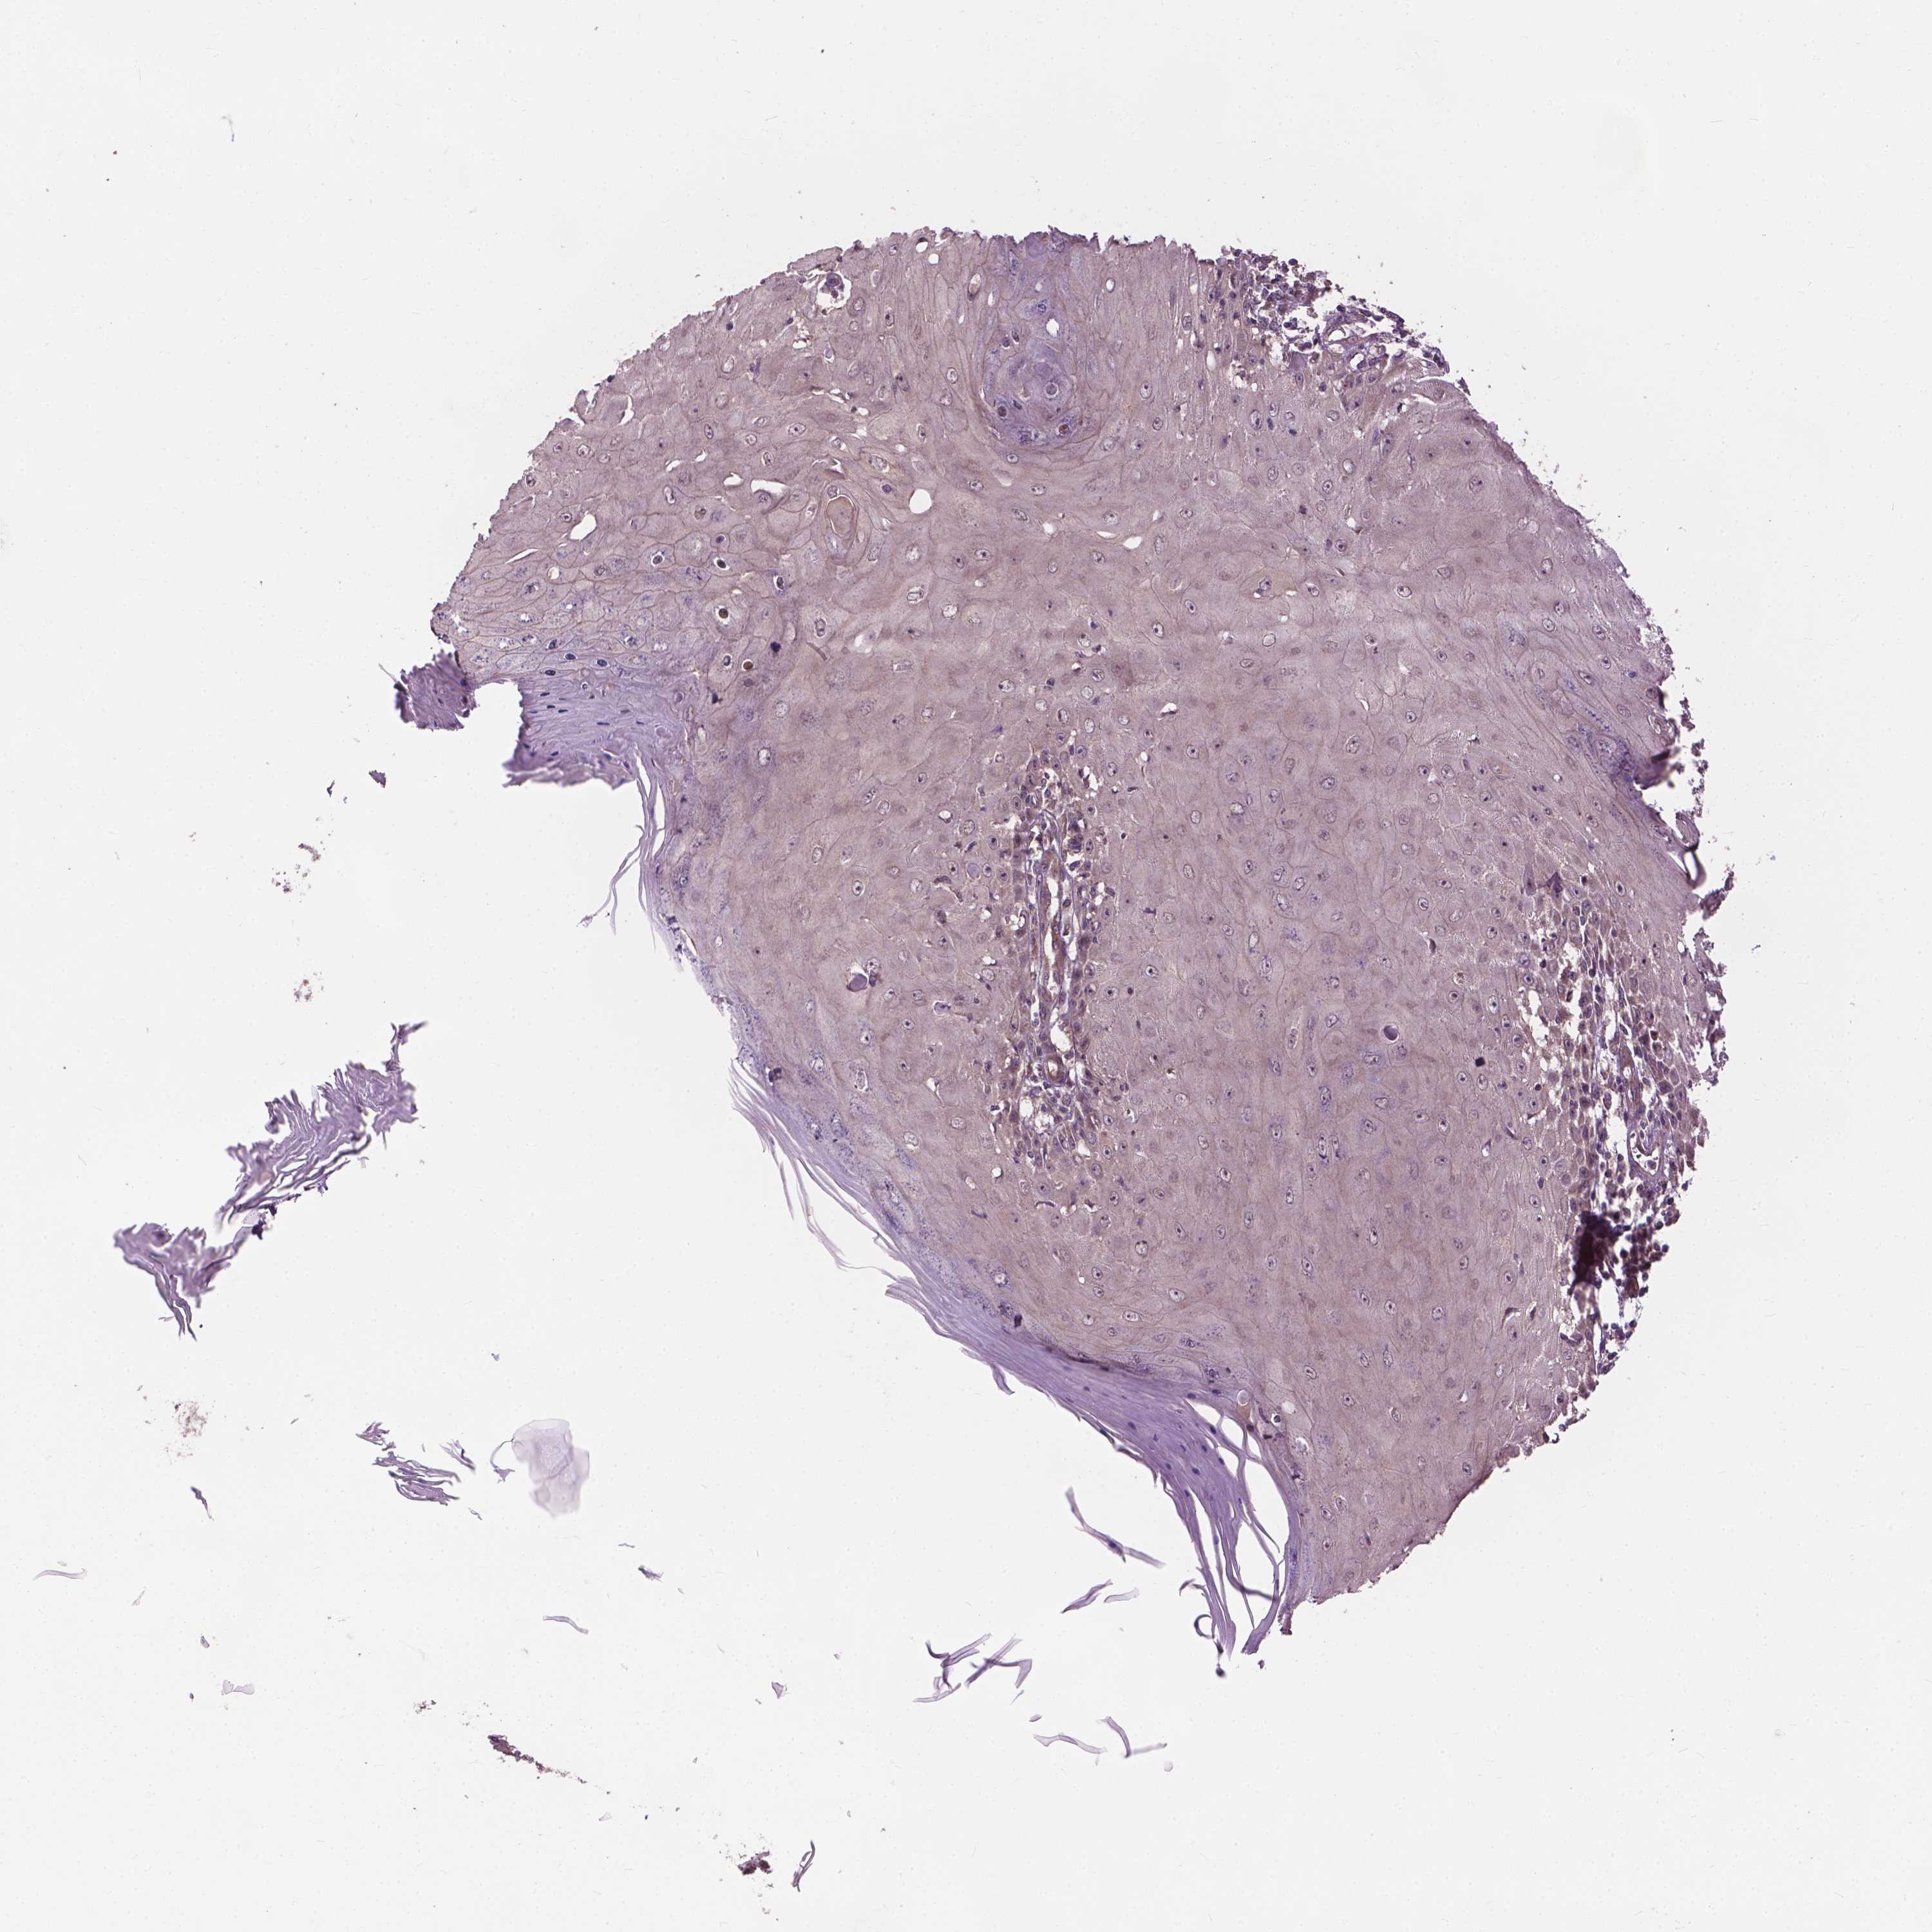

Basal cell and squamous cell cancer

SKIN CANCER - Protein expressioni

A mouse-over function shows sample information and annotation data. Click on an image to view it in a full screen mode. Samples can be filtered based on level of antibody staining by selecting one or several of the following categories: high, medium, low and not detected. The assay and annotation is described here.

Each image is clickable and will lead to virtual microscopy that enables deeper exploration of all samples and also displays staining intensity scores, fraction scores and subcellular localization as well as patient and tissue information for each sample.

Antibody HPA065425

Antibody CAB069426

Basal cell carcinoma

Squamous cell carcinoma, NOS

BCC, high aggressive